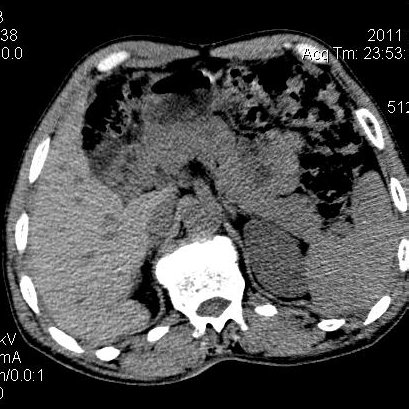

肝左叶发育异常

男性,55岁,骑摩托车摔倒后入院,自述右上腹疼痛

[backcolor=#FF0000]第一次诊断的时候也是这么肯定,可是床旁超声检查并没有发现明显异常,而且患者的一般症状都良好。还好临床只是保守治疗,没有立即手术,第二次复查的时候没有一点变化,又做了MRI检查,没有血肿,

这是一例肝左叶发育异常的,很个性吧~[/backcolor]